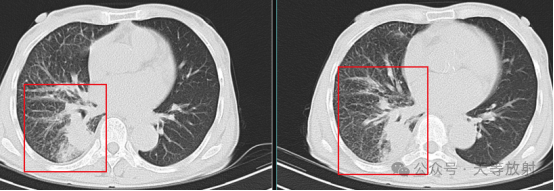

临床表现: 患者主诉咳嗽、咳痰、咯血。 影像学表现肺内弥漫性腺泡状分布磨玻璃影,这些阴影中可见小叶间隔增厚。